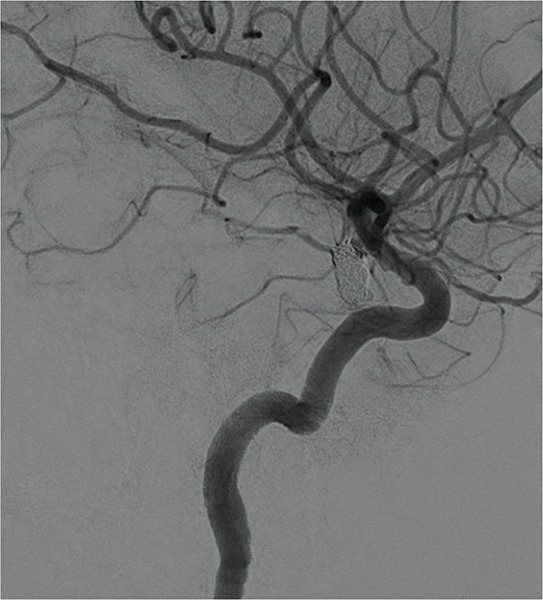

Teaching point: Although computed tomography (CT) is the diagnostic gold standard for acute subdural hematoma, the absence of clear trauma should prompt the use of computed tomography angiography (CTA) to identify potential underlying causes, such as ruptured aneurysms, which can significantly influence treatment decisions.

教学要点:虽然计算机断层扫描(CT)是诊断急性硬膜下血肿的金标准,但如果没有明确的外伤,则应立即使用计算机断层扫描血管造影术(CTA)来识别潜在的潜在病因,如动脉瘤破裂,这对治疗决策有重大影响。